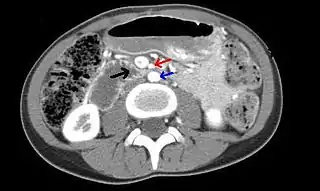

![]() Tomografía computarizada de abdomen y pelvis que muestra compresión duodenal (flecha negra) por la arteria mesentérica superior(flecha roja) y la aorta abdominal (flecha azul). | ||

El síndrome de la arteria mesentérica superior o síndrome de Wilkie es una entidad poco frecuente causada por la compresión de la tercera porción del duodeno entre de la arteria aorta y la arteria mesentérica superior causando dolor y una obstrucción abdominal alta.[1]